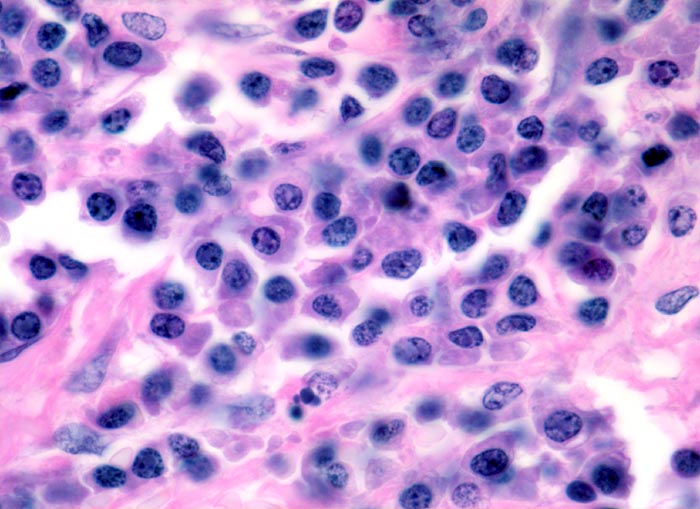

Morphologische Merkmale:

• Knochenmarkstanze mit nodulärer Hyperzellularität des blutbildenden Marks.

• In den hyperzellulären Arealen dichte Rasen neoplastischer atypischer Plasmazellen.

• In dieser Giemsa-Färbung sind die Plasmazellen gut erkennbar. Die Plasmazellen sind polymorph, vereinzelt mehrkernig. Exzentrisch im Zytoplasma lokalisierte vergrösserte Radspeichenkerne . Reichlich violettes Zytoplasma mit paranukleärer Aufhellung. Zellkerne teils mit vergrössertem Nukleolus.

• Ausserhalb der Plasmazellrasen findet sich spärlich residuelles blutbildendes Knochenmark.